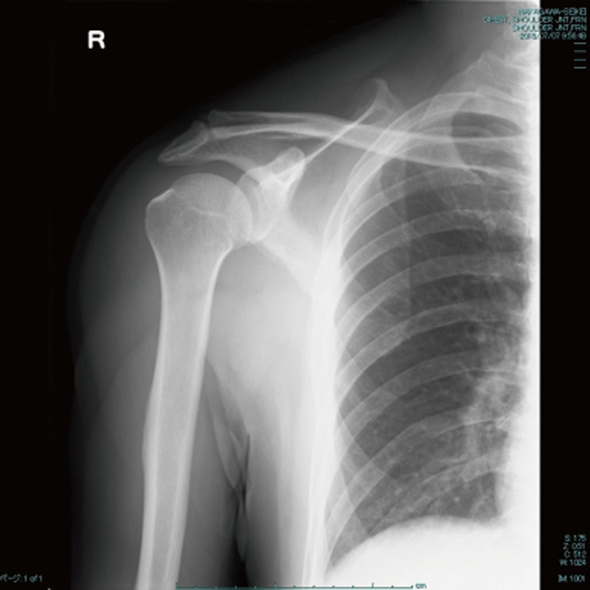

交通事故治療は画像診断が不可欠です。

レントゲンでは、骨折の症状に影響を与えるような経年性変化(加齢変化)を診断します。

エコーは筋や皮下組織の打撲・血腫・神経組織の様子を診断します。